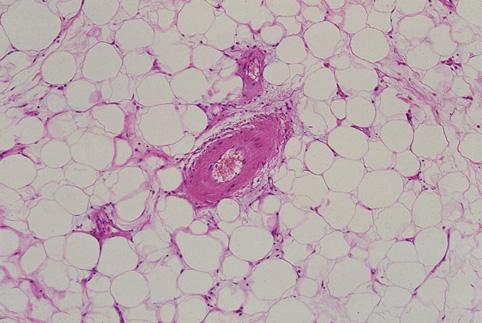

양성 비상피성종양 지방종 (대장)

장중적과 주변부에 수반성의 궤양을 동반한 결장의 지방종

양성 비상피성종양/지방종

대장/하행

35~40